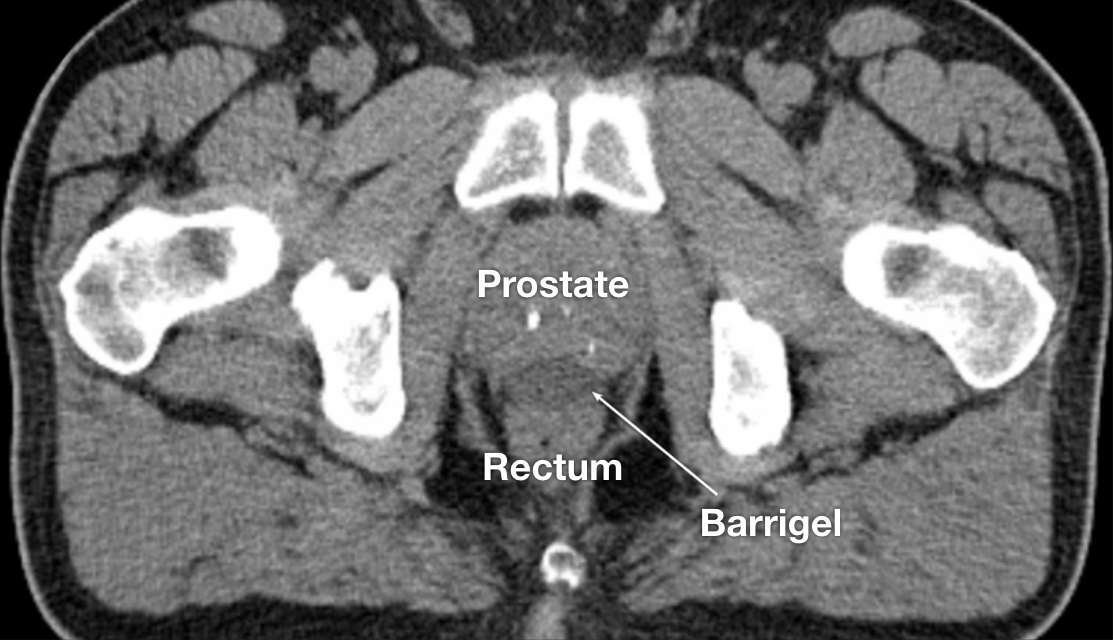

CT image courtesy of Gregory Bell, MD

Interventional Radiologist; Texas, United States